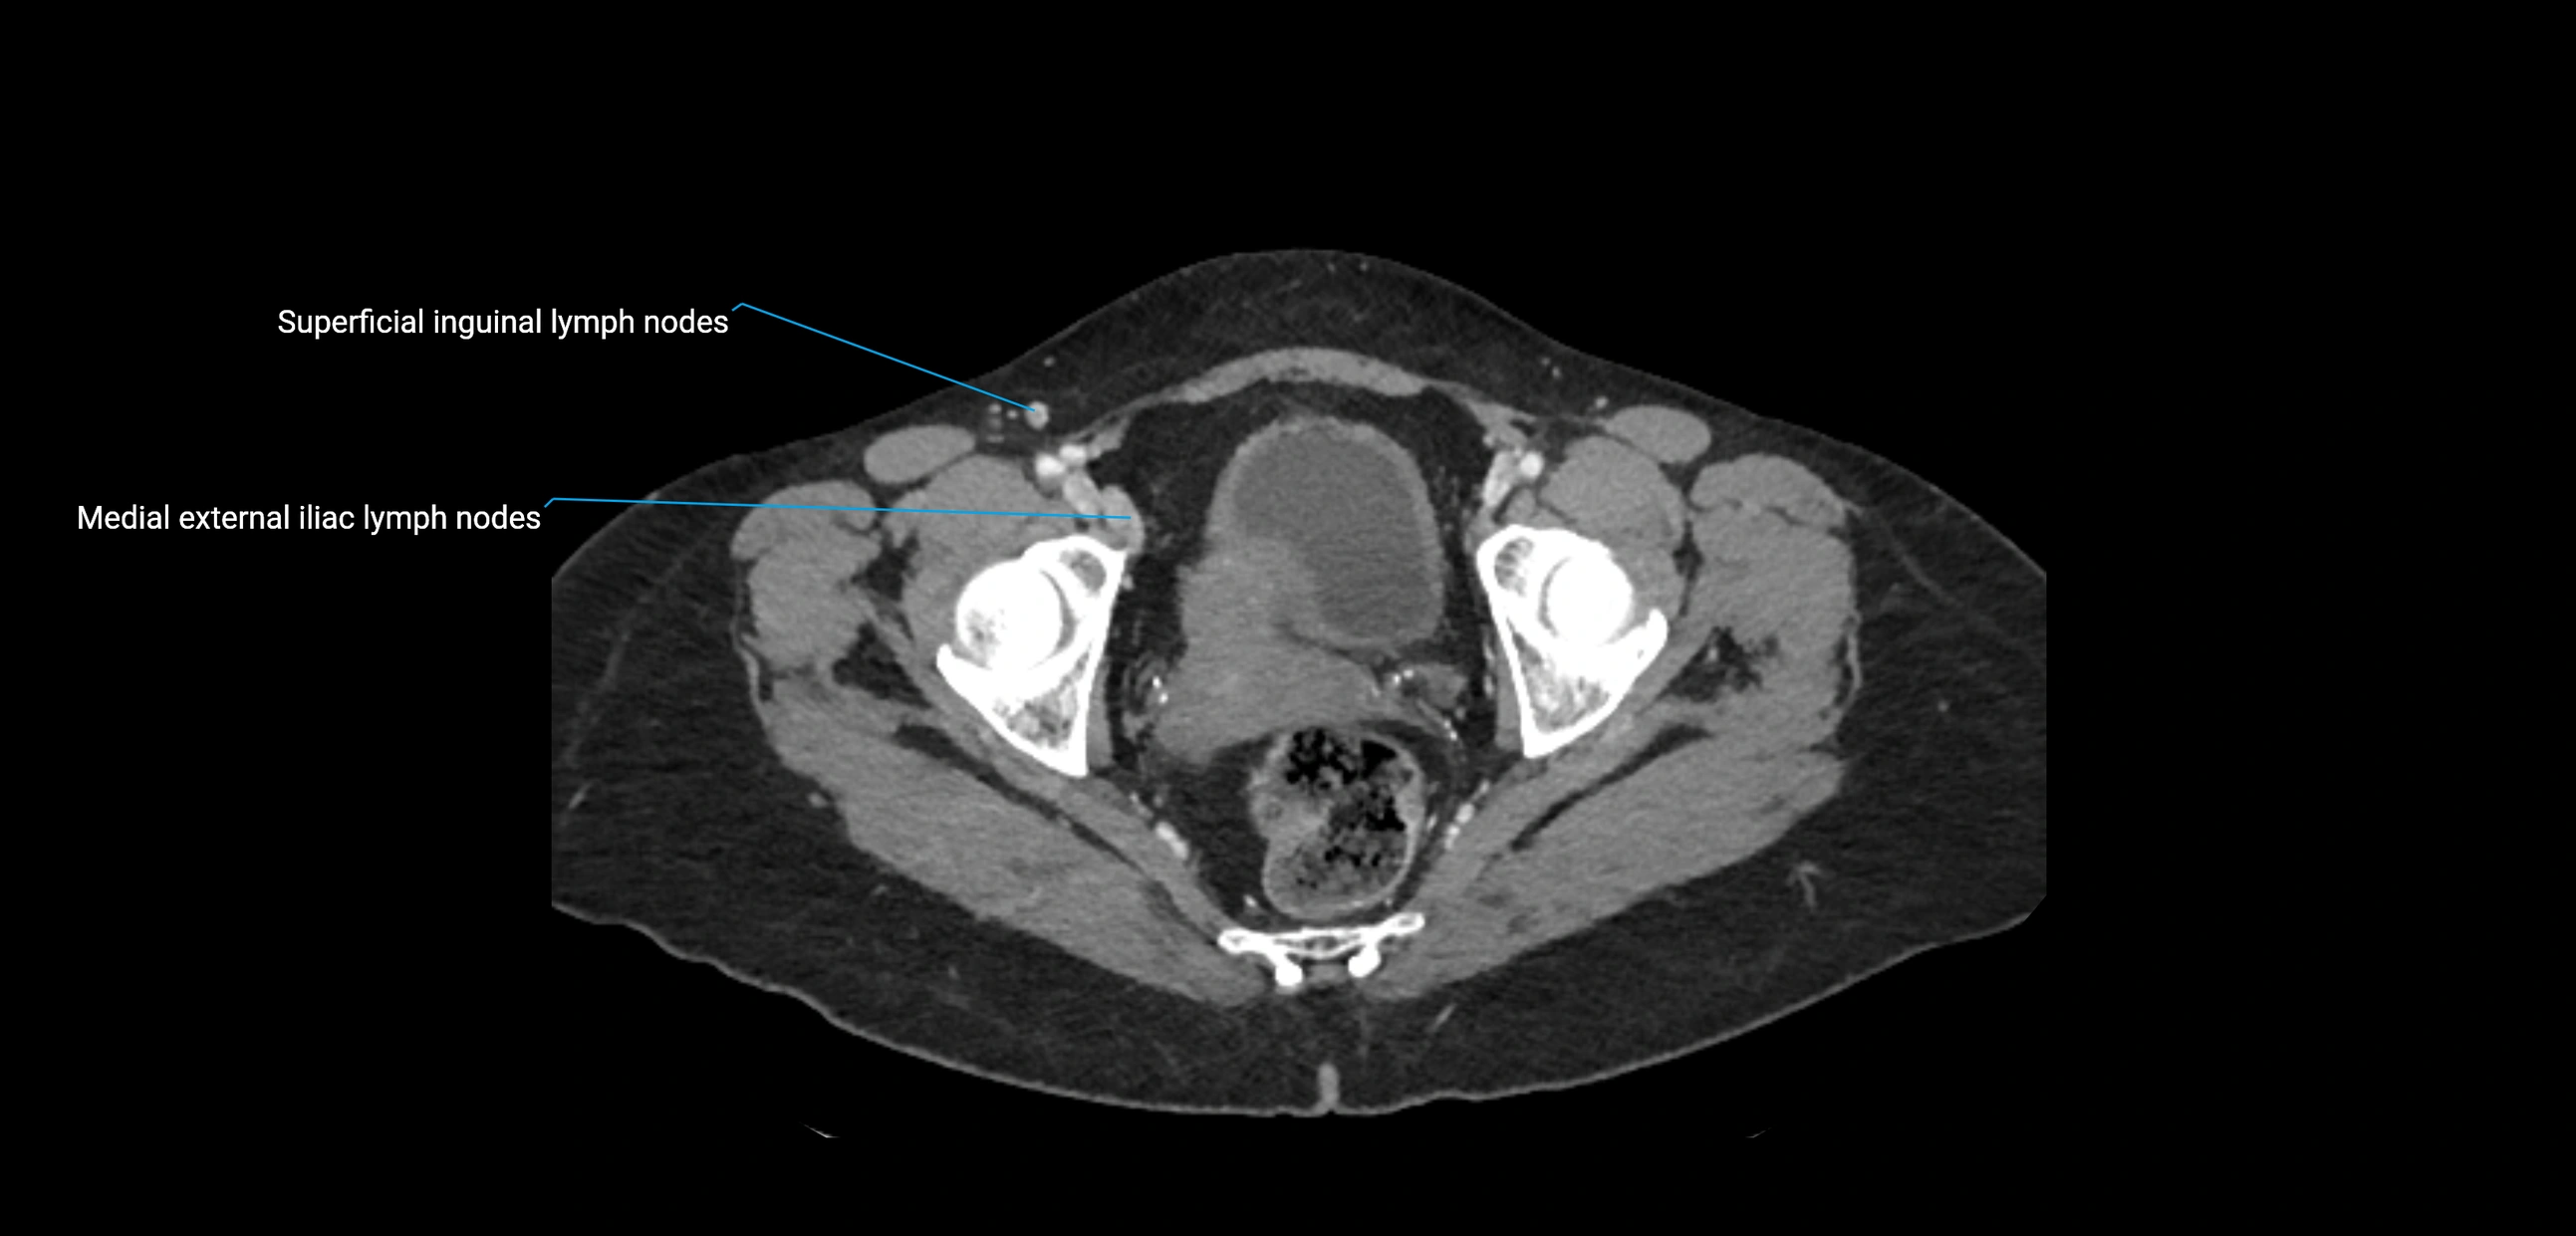

CT image

image